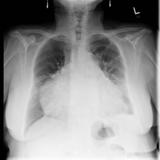

Case 1 PA

Peric calcification

Date: 03/17/2004

Views: 2585